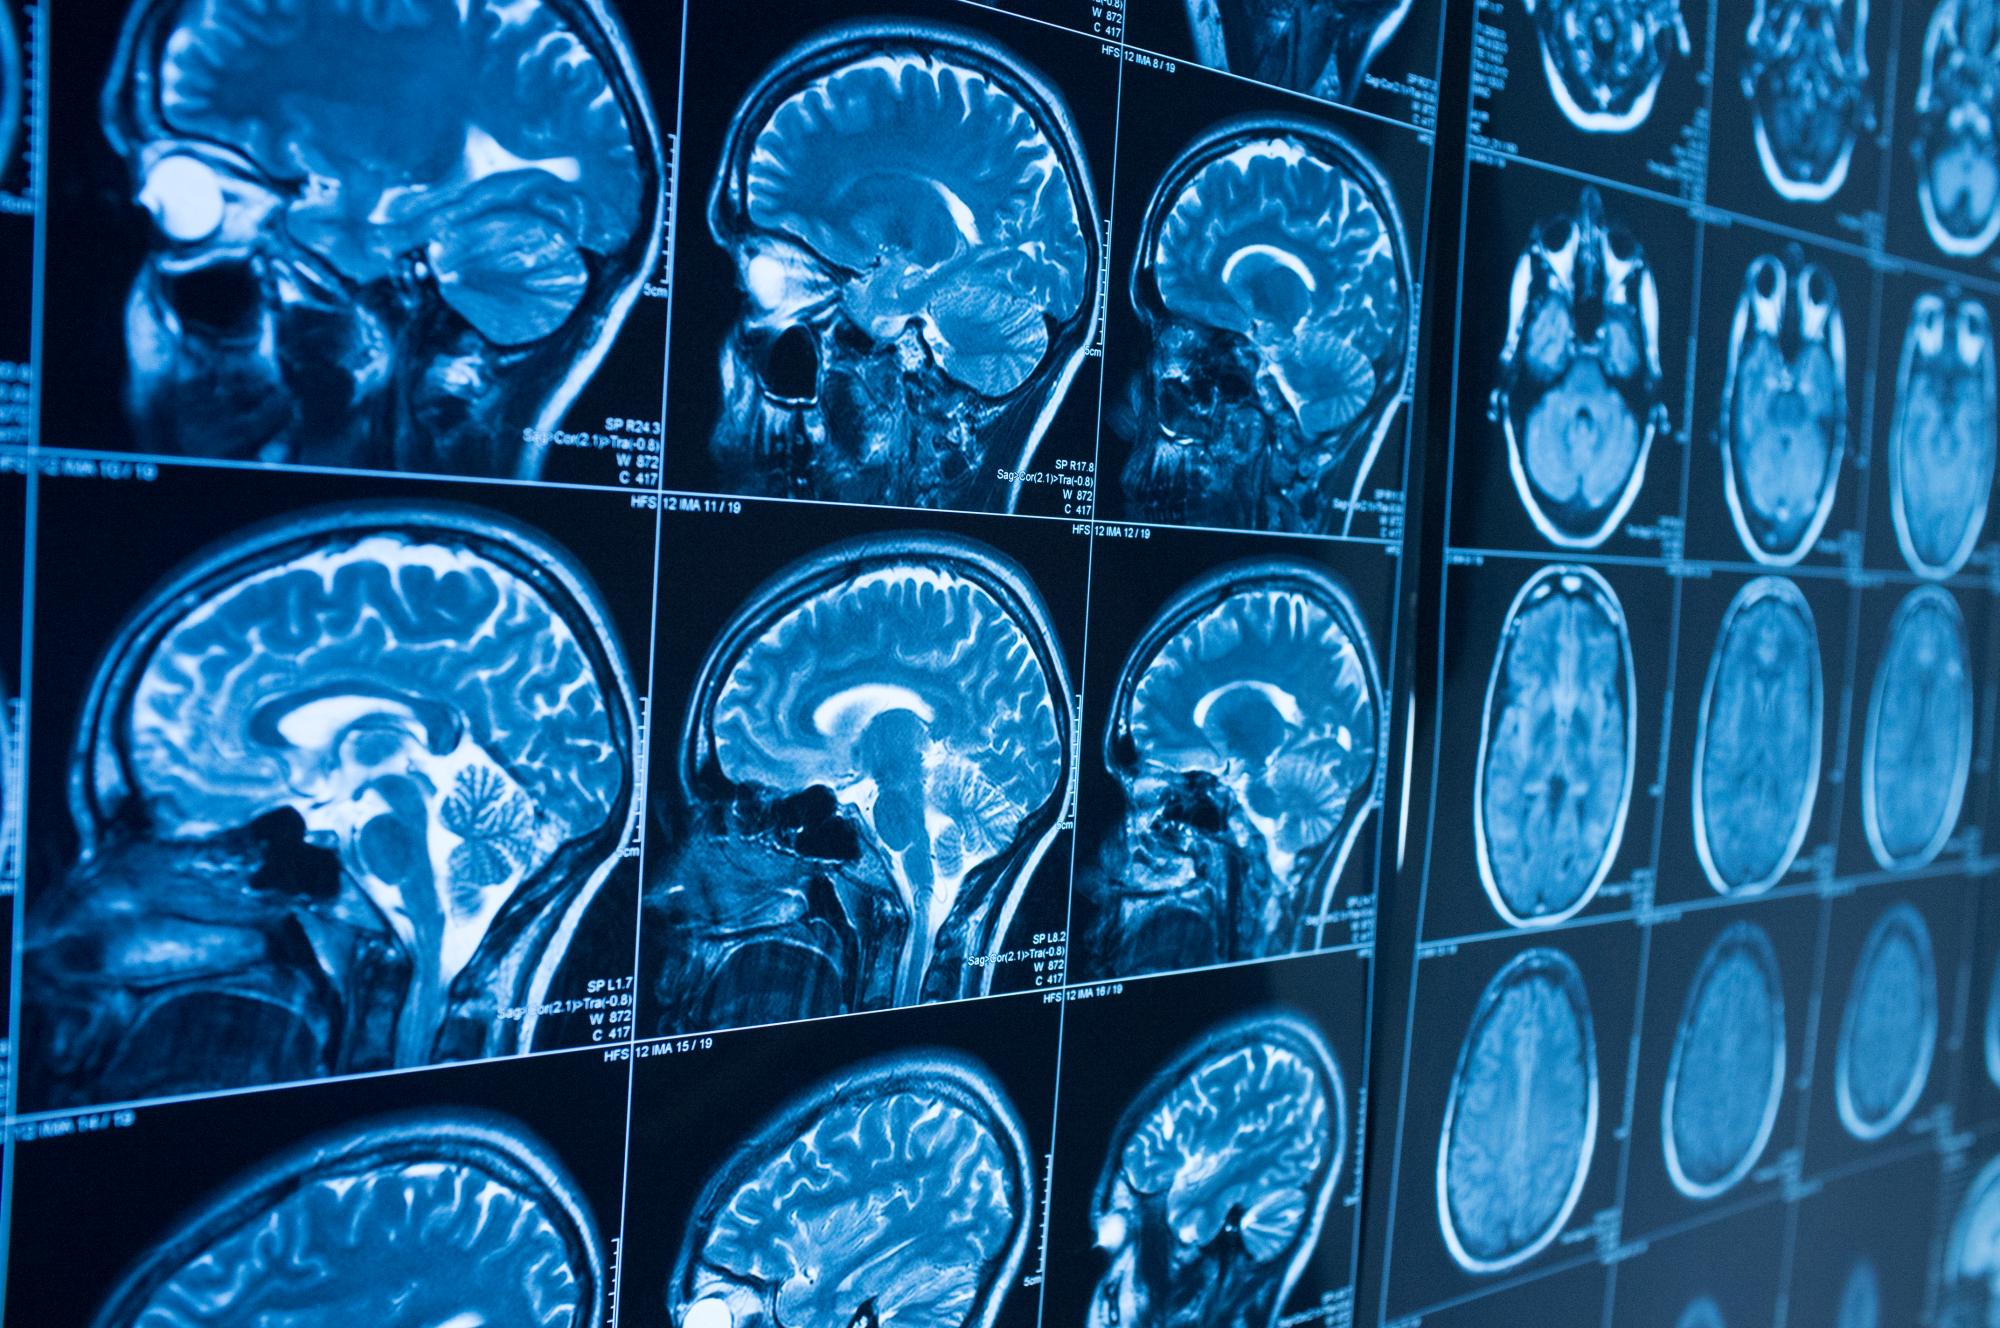

A recent upgrade to the centre has been the addition of an MRI scanner to help with breast cancer diagnosis and treatment. “This new machinery will improve diagnostic accuracy. It will give us a more complete picture and allow us to detect tiny tumours much earlier” explains Dr. Kotziamanis.